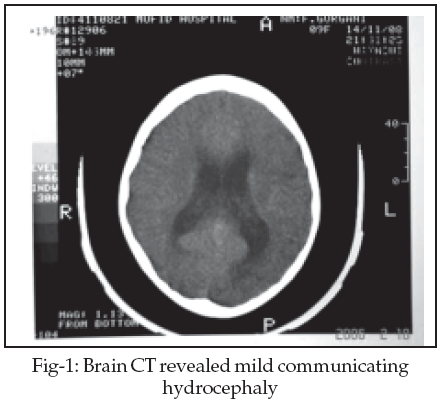

Brain CT revealed mild communicating hydrocephaly and brain MRI showed patchy hyperintense areas in pons, periventricular white matter, parietal, temporal, and frontal lobes in T2W images (Fig-1,2). At first with impression of Acute Disseminated Encephalomyelitis (ADEM), she was treated with methylprednisolon without any improvement. She developed fever and nuchal rigidity after third day of treatment and was referred to infectious ward.